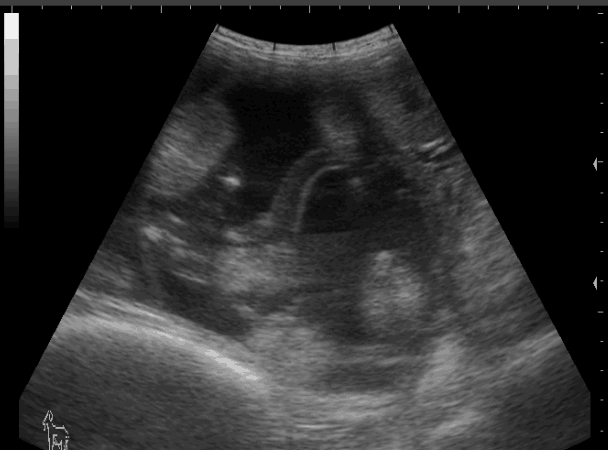

羊用B超仪观察母羊妊娠B超图像